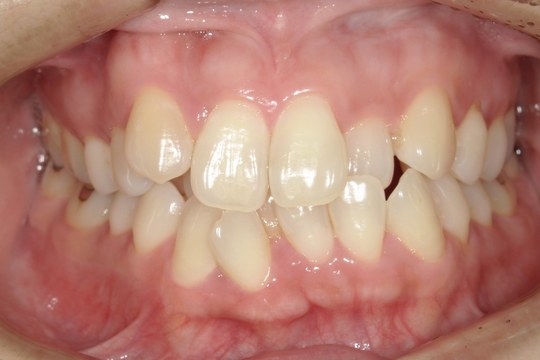

After

浜松市中央区・自動車学校前駅のインビザラインの症例

N.T 20代女性

上の前歯が出ているのが気になる、左下の第二小臼歯が内側に入っているのが気になるとの主訴でご来院。

上の前歯を下げて左下の第二小臼歯を外に移動させることで気になっていた上顎前突を改善しました。

治療の期間:R4. 4/22〜R6. 11/2

治療の価格:66万円